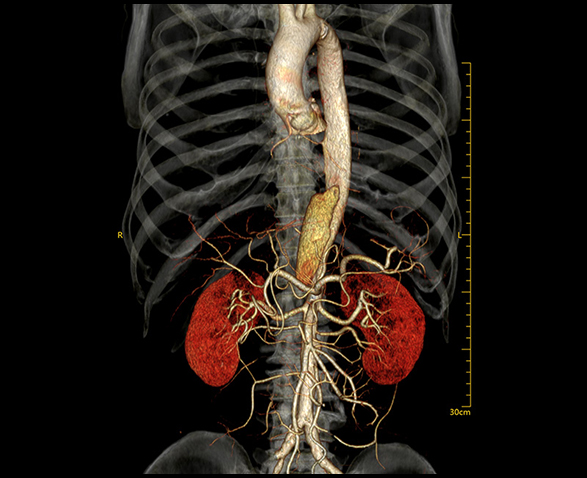

- Dėl itin greito 0,259 s sukimosi greičio „NeuViz Prime“ galima gauti tikslesnius vaizdus kraujotakos sistemoje.

- Mikro fokusavimo taškas, keturgubos atrankos technologija veikia su iHD (izotropinės didelės raiškos) ir 1024 matrica, erdvinė skiriamoji geba gali siekti 30 lp/cm 0 %MTF.